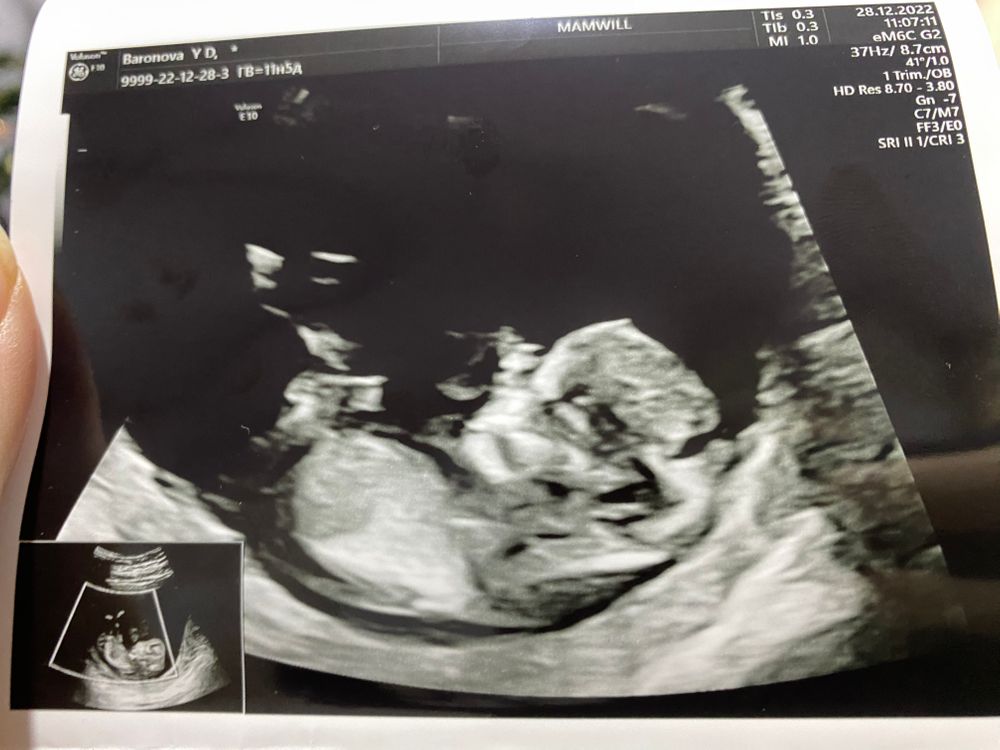

Скрининг 1

Замечательный малышок! Пусть и дальше растет и все будет хорошо!!!

Мне кажется, девуля у вас) На первом кадре видно.

Nysha, я когда пришла, видно волновалась и он такие пируэты выдавал, не сфоткать, а когда я успокоилась - уснул, да еще и рукой лицо закрыл, понятно что фотка неудачная будет) врач даже просила встать походить, еще раз посмотрели, а он все равно вот как застыл в таком положении 😁

Похоже на девочку, но это не точно.